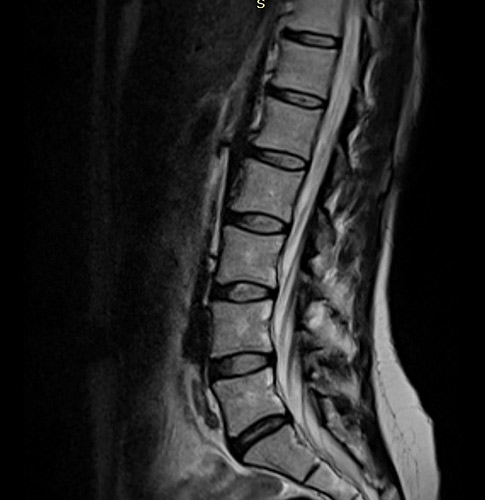

Φωτό 1: Εδώ βλέπουμε τη μαγνητική τομογραφία γυναίκας κοντά στα 30, με πάρα πολύ έντονα συμπτώματα ισχιαλγίας σε βαθμό που χρειάστηκε να κάνει επισκληρίδιο χορήγηση φαρμάκου για να ηρεμήσει, χωρίς απολύτως κανένα εύρημα στην εξέταση που να συνηγορεί στη σοβαρότητα του πόνου.